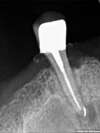

A la suite d'une vive douleur, nous découvrons une nécrose de la dent sous la couronne et un kyste très important qui en découle.

Il envahit le sinus et le repousse même. |